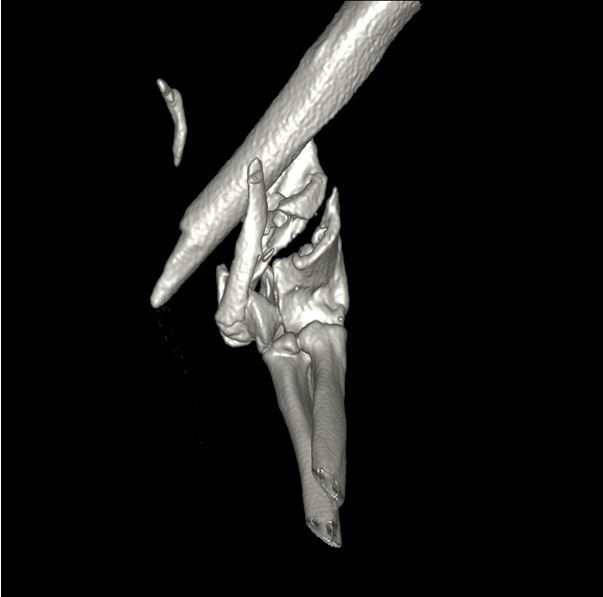

A computed tomography (CT) scan was performed to establish whether the articular component could be reconstructed.

3D CT reconstruction of the left elbow prior to surgery

Despite the catastrophic nature of the fracture it was possible to reconstruct the articular surface using a lag screw across the humeral condyle. The condyle was reattached to the shaft of the humerus using bilateral PAX locking plates. 12 weeks following surgery the cat had returned to normal activity and follow up radiographs showed complete healing of the fracture.